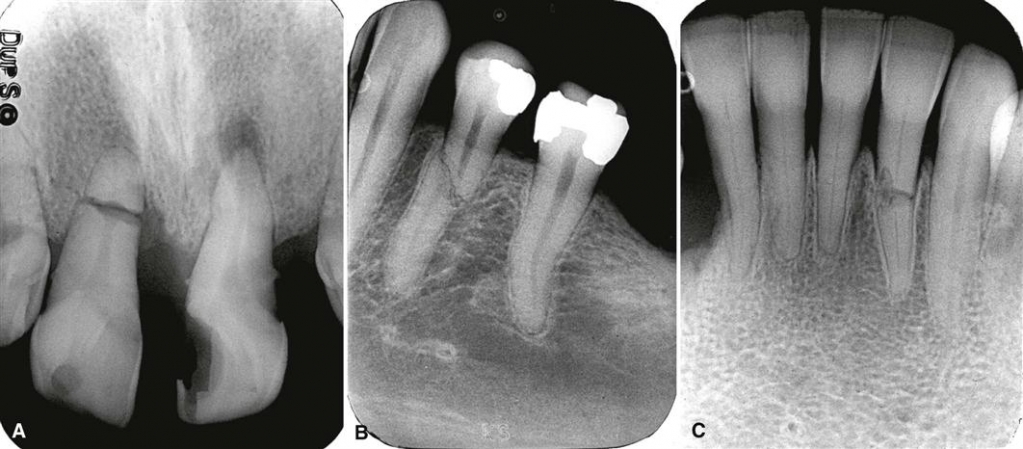

Для случаев восстановления зубов фронтальной группы, например, при переломе корня переднего зуба, необходимо закрыть эстетический дефект как можно раньше, данный протокол несколько изменили.

Имплантация Immediate Load – имплантация с немедленной нагрузкой. Также она называется одноэтапной имплантацией, так как сразу же после установки имплантата в костную ткань, на имплантат фиксируется временный зубной протез, выведенный из прикуса, это позволяет без полного приживления искусственного корня зуба с костью давать небольшие нагрузки на временные зубы. После полной остеоинтеграции устанавливается постоянная коронка.

Чаще всего имплантация с немедленной нагрузкой проводится сразу же после удаления больного зуба. Важным условием для одномоментной имплантации является наличие здоровых зубов рядом с удаленным зубом, которые примут на себя нагрузку и позволят имплантату лучше прижиться. Преимущества одноэтапной имплантации с моментальной нагрузкой – за одно посещение стоматолога можно восстановить утраченный зуб и избежать дополнительного хирургического вмешательства. Пример такой операции, проведенной у нас в клинике и описание технологии, здесь.